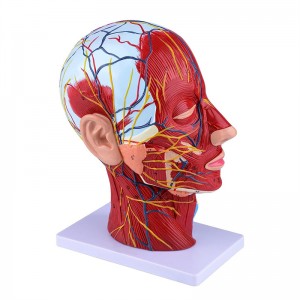

ਮਨੁੱਖੀ ਅੱਧਾ ਸਿਰ ਅਤੇ ਗਰਦਨ ਅਨਾਟਮੀ ਮਾਡਲ ਸਤਹੀ ਨਿ ur ਰੋਵਸਕੂਲਰ ਮਾਡਲ

ਮਨੁੱਖੀ ਅੱਧਾ ਸਿਰ ਅਤੇ ਗਰਦਨ ਅਨਾਟਮੀ ਮਾਡਲ ਸਤਹੀ ਨਿ ur ਰੋਵਸਕੂਲਰ ਮਾਡਲ

【1: 1 ਦਾ 1 ਜੀਵਨ ਬਚਾਉਣ ਵਾਲਾ ਹਿੱਸਾ 1: 1 ਕੁਦਰਤੀ ਵੱਡੇ ਸਿਰ ਅਤੇ ਗਰਦਨ ਸਤਹੀ ਸੰਚਾਲਕ ਨਾਚਲਣ ਮਾਸਪੇਸ਼ੀ ਮਾਡਲ (ਸੱਜੇ ਪਾਸੇ). ਵਧੀਆ ਕਾਰੀਗਰ. ਐਨਾਟੋਮਿਕਲ ਵਿਸ਼ੇਸ਼ਤਾਵਾਂ ਦੀ ਪੂਰੀ ਸ਼੍ਰੇਣੀ ਦੀ ਪੇਸ਼ਕਸ਼.

】 ਐਪਲੀਕੇਸ਼ਨ】 ਇਹ ਮਾਡਲ ਡਾਕਟਰ ਦੇ ਦਫਤਰ, ਸਕੂਲ, ਹੋਸਿਟਲ ਅਤੇ ਕਲੀਨੈਕਸ ਲਈ ਪਹਿਲੀ ਪਸੰਦ ਹੈ. ਡਾਕਟਰ ਅਤੇ ਮਰੀਜ਼ਾਂ ਲਈ ਐਨਾਟਮੀ ਅਤੇ ਫਿਜ਼ੀਓਲੋਜੀ ਕੋਰਸਾਂ, ਪ੍ਰਦਰਸ਼ਨ ਸੰਦ ਲਈ ਸੱਚਮੁੱਚ ਇੱਕ ਵਧੀਆ ਅਧਿਆਪਨ ਸਹਾਇਤਾ.